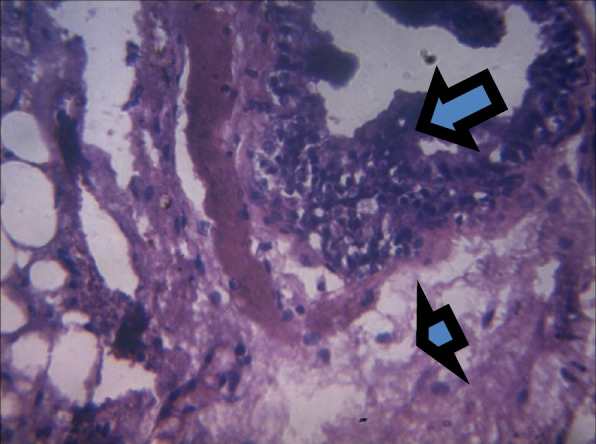

Fig. 6.

Section shows severe epithelial (arrow) and stromal hyperplasia (arrowhead) x 100